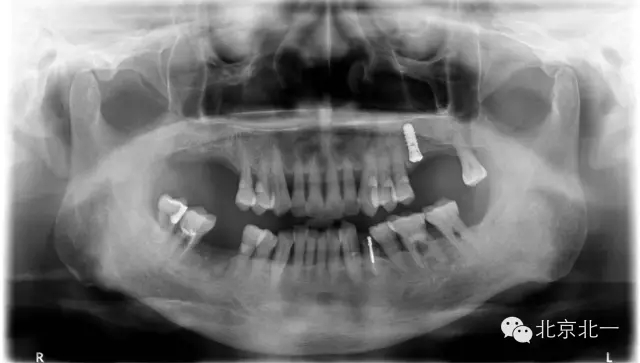

種植問題病例一例

注:每周固定分享一例由北一種植王明老師收集到100例口腔種植問題病例分析。

目的:和更多種植同行一起成長,進步,促進口腔種植專業(yè)健康發(fā)展,幫助年輕種植醫(yī)生規(guī)范口腔種植技術(shù),提供經(jīng)驗與教訓(xùn),減少年輕種植醫(yī)生的專業(yè)錯誤。

病例來源:100例病例中有自己的失敗病例,有同學(xué)分享的失敗或者問題病例,也有學(xué)生的失敗病例,也有大學(xué)院校的失敗病例,也有微信微博分享出來收集的失敗或者問題病例,如有版權(quán)爭議請告知小編會及時安排刪除。

編號027號

患者取模,最后無法脫模,和患者采用石膏取模異曲同工之妙!

分析:患者牙周病,前牙區(qū)間隙大, 倒凹明顯, 醫(yī)生沒有注意填倒凹導(dǎo)致無法脫模, 最后用手術(shù)刀破壞硅橡膠,鋼絲剪剪斷托盤后方取下托盤。非常慶幸不是鋼托盤呀!

預(yù)防措施:取模前切記要充填倒凹即可,特別是牙周病患者,至于什么材料充填可以很多選擇, 最簡單方便的就是蠟片。